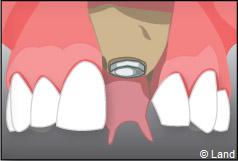

Exemple d’un implant unitaire pour remplacer une dent antérieure manquante.

Le chirurgien-dentiste après une anesthésie locale pratique une incision, puis il décolle la gencive pour accéder à l’os alvéolaire.

L’implant est placé dans l’os le plus souvent par vissage et doit avoir une liaison forte avec l’os. Le praticien replace alors la gencive et pose des points de suture.

Pour finir, une prothèse sera mise sur cet implant qui se comportera comme une racine artificielle.